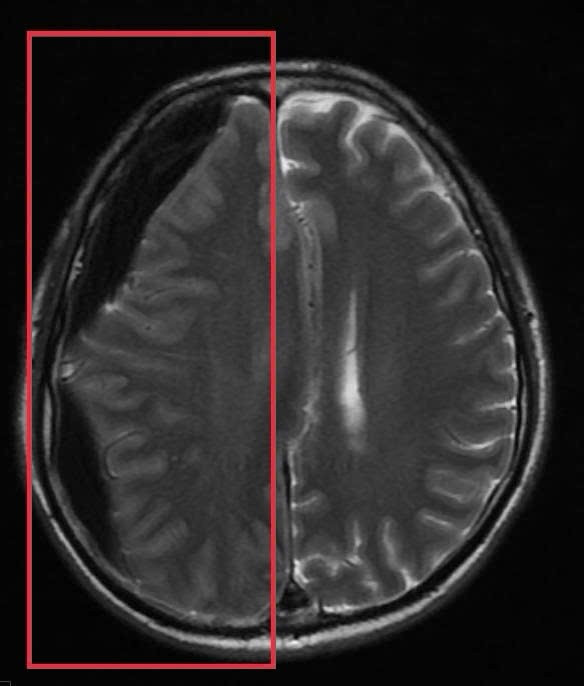

Trước băn khoăn của gia đình, BS Huyền đã tư vấn ưu tiên chụp MRI sọ não. Kết quả chụp MRI sọ não cấp đã xác định người bệnh có khối tụ máu não dưới màng cứng mạn tính kích thước lớn vùng thái dương, gây hiệu ứng khối và đè đẩy đường giữa của não.

Đây là tình trạng đặc biệt nguy hiểm, bởi khối tụ máu có thể tiến triển âm thầm trong nhiều tuần với triệu chứng kín đáo như chậm chạp, giảm trí nhớ, rối loạn ngôn ngữ nhưng có nguy cơ cao dẫn đến liệt vận động, tụt kẹt não, hôn mê và tử vong nếu không được xử trí kịp thời.

Khi tiếp tục hỏi sâu, gia đình cho biết người bệnh từng bị ngã khi khởi phát cơn co giật và có đập đầu nhưng không nhớ rõ mức độ, thời điểm rơi vào khoảng bốn tuần trước – chi tiết này rất phù hợp với thời gian hình thành một khối tụ máu não mạn tính dưới màng cứng - tình trạng có thể tiến triển âm thầm và dễ bị bỏ qua.